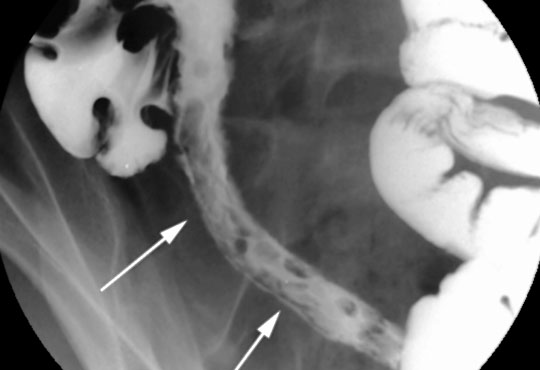

Whole body can be X rayed as and when needed with state of the art high resolution X Ray obtained by Shimadzu Q rad High frequency X Ray machine and Kodak CR System. In addition, Genuine 60 MA portable X Ray unit is available for at Home / bedside X ray.